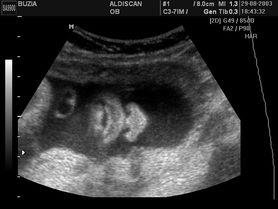

Zdjęcia płodu - twarze

Płód w 11 tygodniu ciąży (zdjęcia 3D)

Płód w 10 tygodniu ciąży (zdjęcia)